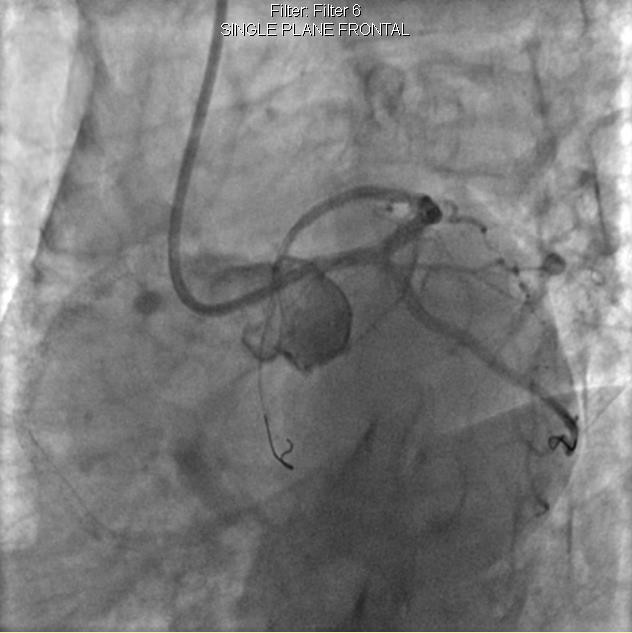

李先生右冠術(shù)前影像

李先生右冠術(shù)后影像

手術(shù)方案確定之后,在心血管內(nèi)三科趙景新主任、介入醫(yī)學(xué)科富孝晨主任的配合下,翟光耀主任親自擔(dān)任主刀,分別依次對(duì)李先生的三支動(dòng)脈進(jìn)行了完全血運(yùn)重建。由于手術(shù)進(jìn)展順利,李先生術(shù)中沒(méi)有任何癥狀,耐受良好,于是成功的將三支動(dòng)脈“一站式”治療!術(shù)中,由于李先生左主干遠(yuǎn)端分叉處存在嚴(yán)重病變,翟光耀主任選擇國(guó)際指南推薦的DK-mini-Crush技術(shù),確保了分叉處兩支主干開(kāi)口均萬(wàn)無(wú)一失。據(jù)悉,DK-mini-Crush技術(shù)是目前冠脈分叉病變領(lǐng)域最為復(fù)雜及難以掌握的介入技術(shù)之一,對(duì)手術(shù)醫(yī)生經(jīng)驗(yàn)、體力均提出了極大的挑戰(zhàn)。極為擅長(zhǎng)復(fù)雜介入技術(shù)的翟光耀主任卻用嫻熟的技術(shù)確保了李先生手術(shù)的成功。